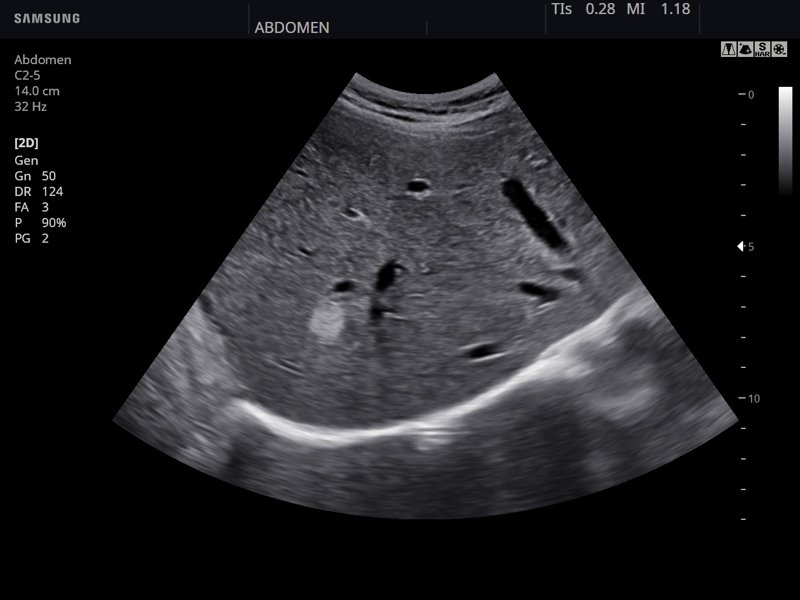

Печень, B-режим (эхограмма №847)

[EN] Эхограмма №847: Печень в B-режиме.

Изображение получено с помощью УЗ сканера HS30 (есть в продаже).